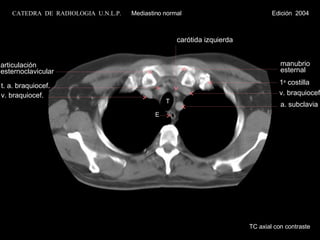

v. braquiocef. TE a. subclavia carótida izquierda t. a. braquiocef. v. braquiocef. manubrio esternal 1 a costilla articulación esternoclavicular TC axial con contraste CATEDRA DE RADIOLOGIA U.N.L.P. Mediastino normal Edición 2004

v. braquiocef. T E a. subclavia carótida izquierda t. a. braquiocef. v. braquiocef. manubrio esternal 1 a  costilla articulación esternoclavicular TC axial con contraste CATEDRA  DE  RADIOLOGIA  U.N.L.P.   Mediastino normal  Edición  2004